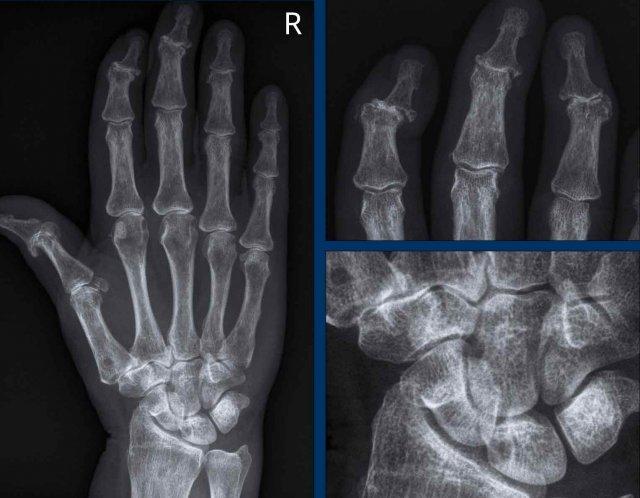

Hình ảnh bào mòn xương vùng rìa điển hình và hẹp khe khớp tại các khớp MCP 3-5.

Lưu ý hình ảnh hẹp khe khớp đồng đều tại các khớp MCP.

Các khớp liên đốt gần (PIP) chỉ biểu hiện hẹp khe khớp tối thiểu.

Đây là trường hợp viêm khớp dạng thấp giai đoạn cuối với các thay đổi bào mòn nặng nề và đứt dây chằng gây trật khớp tại các khớp MCP.

Phân ly xương thuyền – xương nguyệt (mũi tên trắng) là dấu hiệu thường gặp do tình trạng viêm lan tỏa khối xương cổ tay. Cả tình trạng phân ly lẫn viêm đều có thể gây hẹp khe khớp quay – cổ tay.

Lưu ý hình ảnh bào mòn xương đầu dưới xương trụ kèm theo sưng nề phần mềm xung quanh (mũi tên xanh).